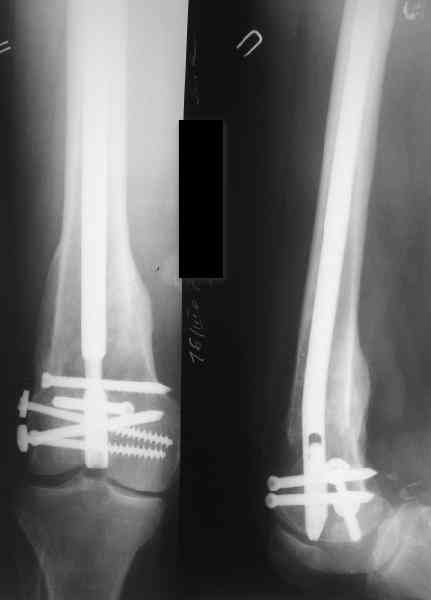

27 марта выполнено удаление блокирующих винтов (сломанный винт пришлось высверливать цапфен-бором), сломанного штифта (дистальный фрагмент удален через канал, образованный разверткой из коленного сустава - image 4),

рассверливание костно-мозгового канала, реостеосинтез штифтом UFN (при проведении штифта в дистальном отломке мы использовали поляризующий винт, диаметр штифта 10 мм). После операции в связи гемартрозом дважды (на 1 и 3 сутки) выполняли пункцию коленного сустава. Сейчас признаков скопления жидкости в полости сустава нет. Послеоперационные рентгенограммы - images 5, 6, 7.